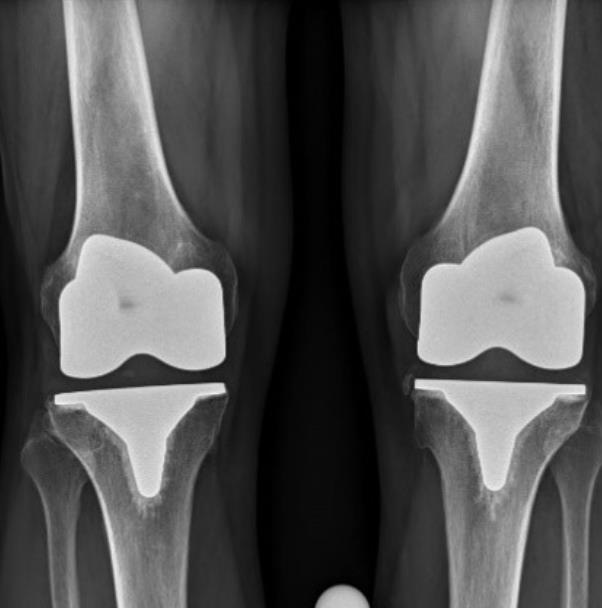

[Blocked from Release] ATTUNE™ Knee System

• The ATTUNE™ Primary Knee System is designed with the goal of addressing the clinical needs of patients, surgeons, and hospital providers around the world.

• Extensive research and science is included in the design to improve functional outcomes for patients1, performance for surgeons, and efficiency for providers.